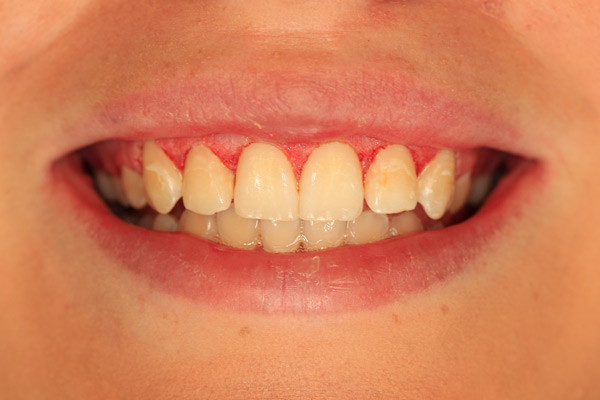

Problem: This patient comes in with badly broken-down teeth and periodontal disease. Her midline is off center. She wants something that will be anchored in so she can eat well and look fabulous.

Plan: Our plan… we removed the remaining teeth and placed four implants on the lower for a fixed/hybrid prosthesis. The upper required bone grafting and then placed eight implants that will support a connector bar prosthesis.

She is happy. We’re happy. Mission accomplished!